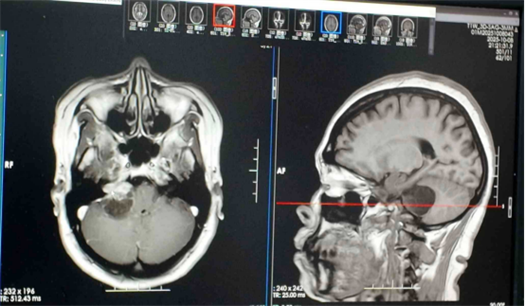

该院神经外科资深专家鲁明主任医师接诊后,发现患者右侧桥小脑角占位压迫听神经,粗测右耳听力明显下降,初步考虑是听神经鞘瘤。

随后,鲁明带领神经外五科为患者行右侧桥小脑角占位切除术。术中,医生在保留听神经和面神经功能的前提下全切肿瘤。

术后病理结果证实是听神经鞘瘤,而群姐的右耳听力恢复清晰,外界声音大一点也不会再嗡嗡响,走路的平衡性也恢复正常。

“听神经鞘瘤是起源于内听道前庭神经鞘膜施旺细胞的良性肿瘤。”鲁明进一步解释,该肿瘤位于内听道及桥小脑角区域,随着体积增大,会逐渐压迫周围的蜗神经、面神经甚至脑干,进而引发听力下降、耳鸣、眩晕等症状,严重时可能危及生命。